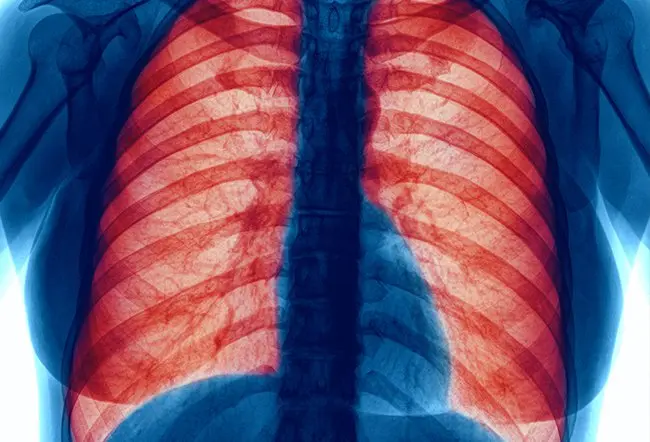

Health Care : ફેફસાના કેન્સરના લક્ષણો જાણો.

Health Care : ફેફસાના કેન્સરને દુનિયાનો સૌથી ખતરનાક કેન્સર માનવામાં આવે છે. તે સૌથી ઝડપથી ફેલાતા કેન્સરમાંનો એક છે. ફેફસાના કેન્સર ત્યારે થાય છે જ્યારે ફેફસામાં અસામાન્ય કોષો અનિયંત્રિત રીતે વધવા લાગે છે. આ કેન્સર પહેલા ફેફસામાં વધે છે. પરંતુ તે શરીરમાં અન્યત્ર હાજર કેન્સરથી ફેફસામાં પણ ફેલાઈ શકે છે. આને મેટાસ્ટેટિક કેન્સર કહેવામાં આવે છે. જો ફેફસાના કેન્સરની સમયસર સારવાર ન કરવામાં આવે તો, તે ફેફસાની બહાર ફેલાઈ શકે છે અને પરિસ્થિતિને ગંભીર બનાવી શકે છે. તેથી, ફેફસાના કેન્સરના શરૂઆતના લક્ષણો જાણવું ખૂબ જ મહત્વપૂર્ણ છે.